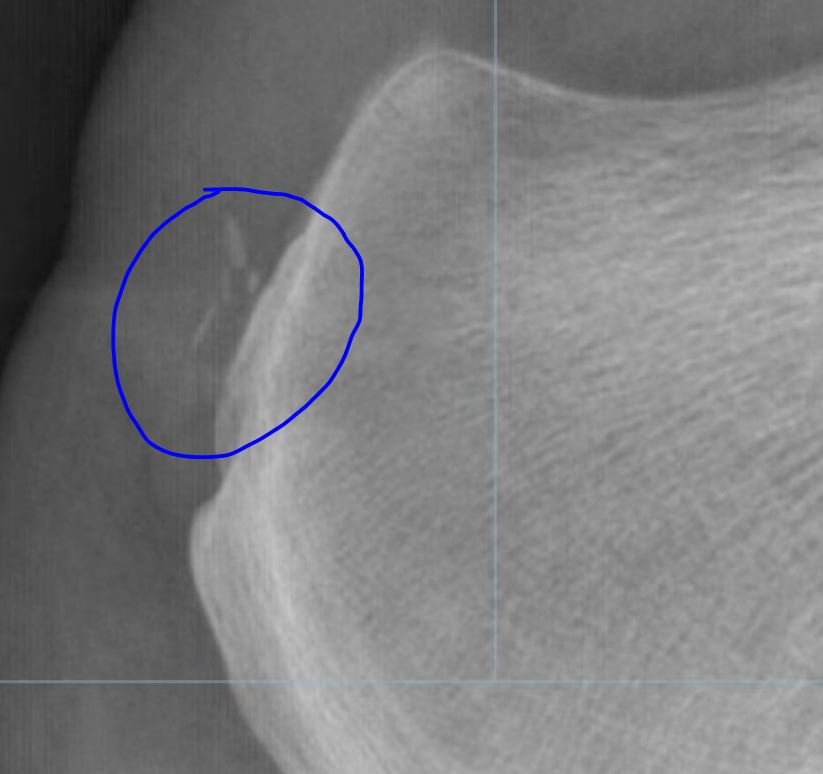

跟腱钙化是肌腱钙盐沉积导致,钙化的跟腱在X光下会表现为高亮度,和骨骼的亮度是相接近的。如果患者长时间进行剧烈运动,或进行繁重体力劳动等,都容易反复牵拉跟腱部位的胶原纤维,从而引起局部组织韧带损伤,出现跟腱钙化。在出现跟腱钙化后,可能表现为不能长时间站立、走路疼痛、跟腱水肿等症状

还有一种跟骨形态畸形:Haglund综合征—Haglund病是指跟骨后上部异常突起,跟骨后上方和跟腱之间的滑囊在反复的机械撞击下产生的炎性症状。 这种情况下保守治疗无效也应该手术治疗,磨除骨刺。